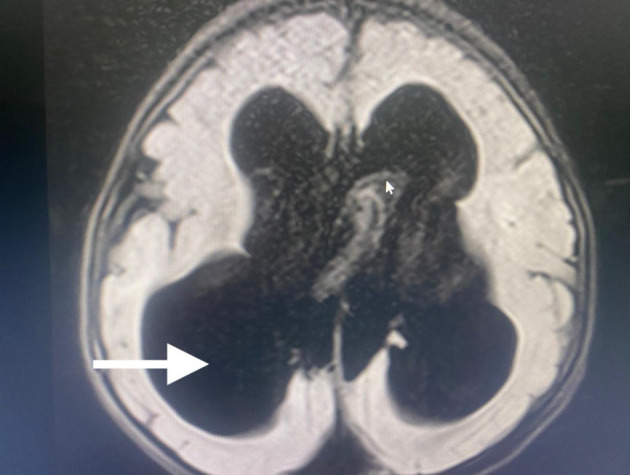

Dandy-Walker综合征是一种罕见的后窝先天性畸形,具有独特的麻醉挑战,包括气道管理困难、意识改变、脑积水和术后通气时间延长的可能性。脑积水是最常见的症状,可使通气和插管复杂化,而脑干受累,以及胼胝体发育不全、脑桥发育不全和髓质呼吸中心扭曲,可能导致术后通气时间延长。这种情况下的麻醉管理需要彻底的气道评估,为潜在的气道困难做准备,颅内压监测和控制,以及全静脉麻醉(TIVA)以促进快速急救。我们描述了一例3岁男性大头畸形、运动障碍、认知发育迟缓和精神状态改变的病例,在没有肌肉松弛剂的情况下,在仔细的气道准备和颅内压控制下,计划在TIVA下放置脑室-腹膜分流术。据我们所知,这是首例用这种方法治疗Dandy-Walker综合征的病例。

Dandy-Walker syndrome is a rare congenital malformation of the posterior fossa that presents unique anesthetic challenges, including difficult airway management, altered consciousness, hydrocephalus, and potential for prolonged postoperative ventilation. Hydrocephalus, the most common finding, can complicate ventilation and intubation, whereas brainstem involvement, along with agenesis of the corpus callosum, pontine hypoplasia, and distortion of the medullary respiratory centers, may contribute to prolonged postoperative ventilation. Anesthetic management in such cases requires thorough airway assessment, preparation for potential airway difficulties, intracranial pressure monitoring and control, and total intravenous anesthesia (TIVA) to facilitate rapid emergence. We describe the case of a 3-year-old male with macrocephaly, movement disorders, delayed cognitive development, and altered mental status, scheduled for ventriculoperitoneal shunt placement under TIVA without muscle relaxants, with careful airway preparation and intracranial pressure control. To our knowledge, this is the first reported case of Dandy-Walker syndrome managed in this manner.